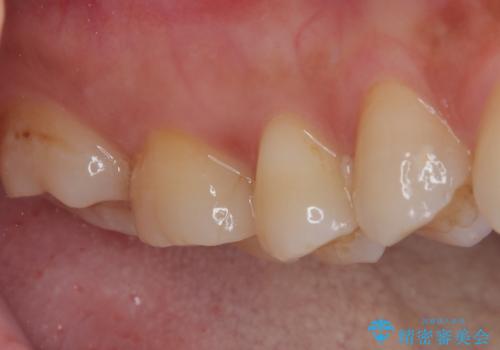

インプラント治療をきっかけに、銀歯を全てセラミックに替えていきました。

人の目を気にせずに、大きく口を開けて笑えるようになりました。